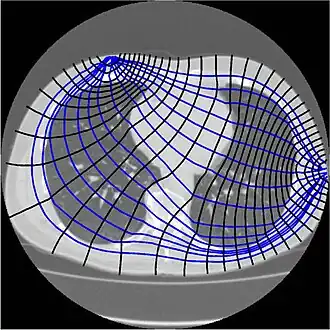

A cross section of a human thorax from an X-ray CT showing current stream lines and equipotentials from drive electrodes. Note how lines are bent by the change in conductivity between different organs.[1] | |

Since free ion content determines tissue and fluid conductivity, muscle and blood will conduct the applied currents better than fat, bone or lung tissue.[2] This property can be used to construct images.[4] However, in contrast to linear x-rays used in computed tomography, electric currents travel three dimensionally along all the paths simultaneously, weighted by their conductivity (thus primarily along the path of highest conductivity, but not exclusively). Image construction can be difficult because there is usually more than one solution for a three-dimensional area projected onto a two-dimensional plane.

Absolute EIT approaches are targeted at digital reconstruction of static images, i.e. two-dimensional representations of the anatomy within the body part of interest. As mentioned above and unlike linear x-rays in Computed Tomography, electric currents travel three-dimensionally along the path of least resistivity, which results in partial loss of the electric current applied (impedance transfer, e.g. due to blood flow through the transverse plane).[3][18][19] This is one of the reasons why image reconstruction in absolute EIT is so complex, since there is usually more than just one solution for image reconstruction of a three-dimensional area projected onto a two-dimensional plane.[4][18] Another difficulty is that given the number of electrodes and the measurement precision at each electrode, only objects bigger than a given size can be distinguished.[26][27] This explains the necessity of highly sophisticated mathematical algorithms that will address the inverse problem and its ill-posedness.